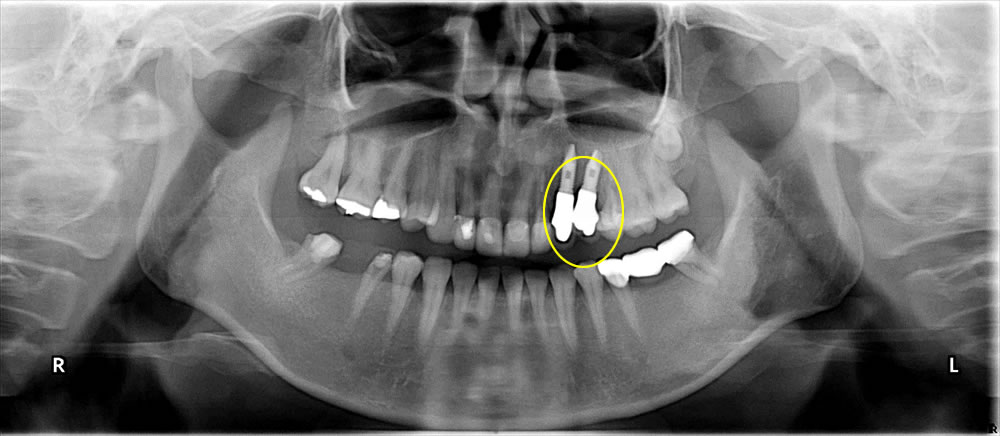

【レントゲン画像(術前)2016年10月14日】

こちらの患者さまは、1週間前より左上顎の3番・4番目の歯が痛むとのことで、ご来院されました。左上顎の3番・4番目の歯は、金属のかぶせ物が装着され、連結されていました。また、当該歯はともに打診痛、圧痛、動揺の他、3番目の歯について大きな虫歯が確認できました。下顎前歯部に咬耗があり、咬合状態はディープバイト(上顎の歯の咬み合わせが深い状態)でした。歯周組織検査においては、歯周ポケットは全顎的に3~5mm程度で中等度の歯周病。既往歴および全身所見に特記事項ありません。

口腔内の状態を把握し、適切なインプラント手術を実施するため、デンタルエックス線写真、パノラマエックス線写真、CT撮影、歯周病検査、唾液検査を実施しました。